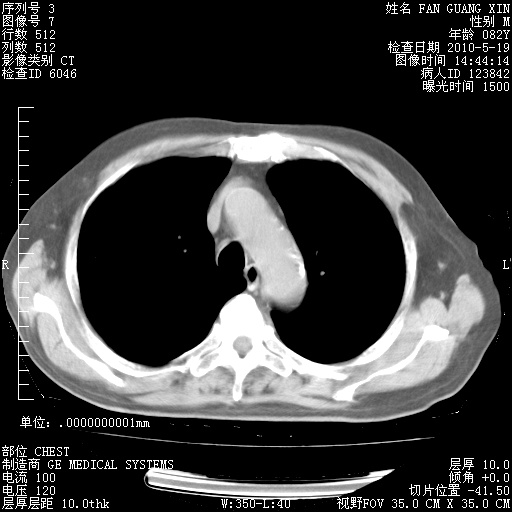

可改为口服强的松40-50mg/d治疗,若病情仍稳定,胸部阴影不再吸收可逐渐减量